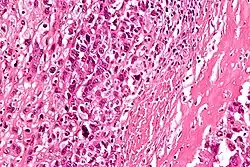

Au microscope la caractéristique de l'ostéosarcome est la présence d'ostéoïde (formation osseuse) dans la tumeur. Les cellules tumorales sont très pléomorphes (anaplasiques), certaines sont géantes, et de nombreuses mitoses sont atypiques. Ces cellules produisent des ostéoïdes décrivant des travées irrégulières (amorphes, éosinophiles / roses) avec ou sans calcification centrale (hematoxylinophilic / bleu, granulaire) - os de la tumeur. Les cellules tumorales sont incluses dans la matrice ostéoïde. Les ostéosarcomes peuvent présenter des cellules géantes ostéoclastiques comme multinucléées[7].

Selon les caractéristiques des cellules tumorales présentes (qu'elles ressemblent à des cellules osseuses, à des cellules cartilagineuses ou des cellules de type fibroblaste), la tumeur peut être classée en trois sous-types d’ostéosarcomes dit conventionnels de haut grade (75 % à 80 % des plus fréquents dans le cancer pédiatrique)[8] :

- ostéosarcome ostéoblastique : 70 %, majoritaire ; les cellules ostéoblastiques produisent une matrice ostéoïde immature. En condition physiologique, cette matrice se minéralise et donne lieu à l’apparition d’un os. Au contraire, lors de cancer des os, cette matrice n’a pas le temps de se minéraliser et donc de durcir ;

- ostéosarcome chondroblastique : 12 % ;

- ostéosarcome fibroblastique : 10 %.